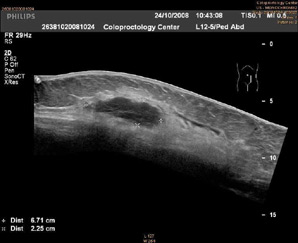

Панорамное сканирование 2D Ультразвуковое исследование передней брюшной стенки (в толще определяется гематома).